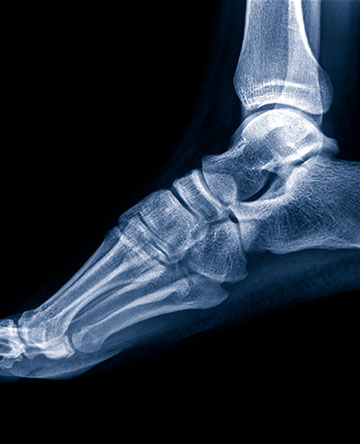

Ankle replacement is a surgical option for patients with arthritis of the ankle. This operation can relieve pain and maintain motion in the arthritic ankle joint and is an alternative to an ankle fusion, which can relieve pain but eliminates motion in the joint.

Ankle replacement surgery is often appropriate for patients who avoid high-impact activities, such as skiing, basketball and football. Ankle replacement may be better suited for people with near-normal alignment of the ankle and no history of infection in the ankle joint. Most patients who have ankle replacement surgery have osteoarthritis, rheumatoid arthritis or arthritis caused by a prior trauma, such as a broken ankle.